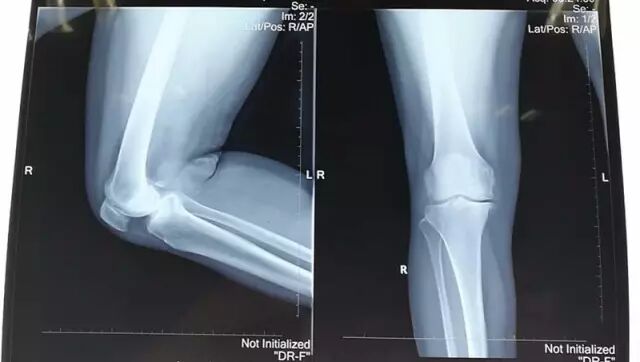

↑图:术前拍片情况